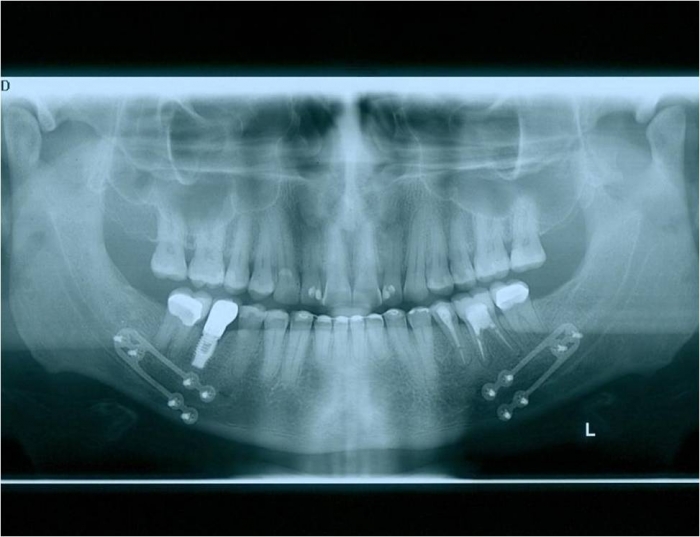

Raio x inicial